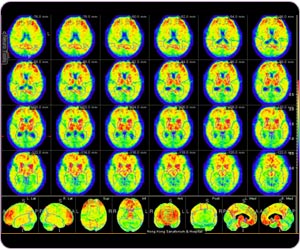

11C标记PIB脑部正电子扫描:基於区域的定量分析